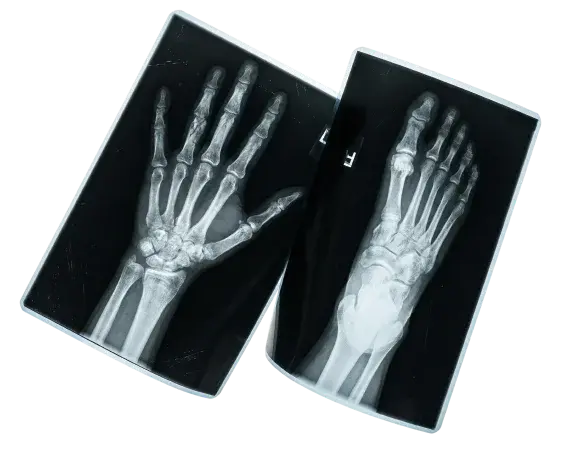

Хирургия кисти

Направление, объединяющее несколько ключевых областей: травматологию, нейрохирургию, сосудистую хирургию, пластическую хирургию, хирургию мягких тканей и микрохирургию.

Мы предлагаем комплексное лечение заболеваний и травм кисти, руки и запястья.

Хирургия стопы

Комплексное лечение заболеваний и травм стопы и голеностопного сустава. Мы специализируемся на коррекции деформаций, восстановлении функций и устранении боли.